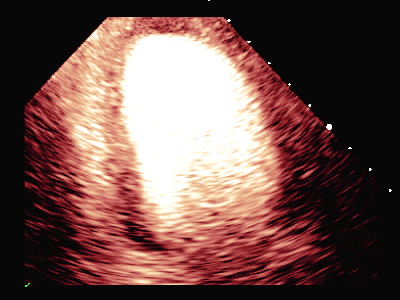

超声负荷造影提示:

负荷前左室壁未见明确节段性运动异常,左室各节段心肌灌注充盈良好。

平板负荷量达89%时,该时患者心率157次/分,出现短阵性室性心动过速,即刻超声造影检查显示:负荷后左室前间隔中段、室间隔心尖段、侧壁中段、心尖段、下壁心尖段、前壁心尖段及心尖帽运动减弱。室间隔心尖段及心尖帽心肌灌注稀疏。

患者休息后检查:左室壁未见明确节段性运动异常,左室各节段心肌灌注充盈良好。